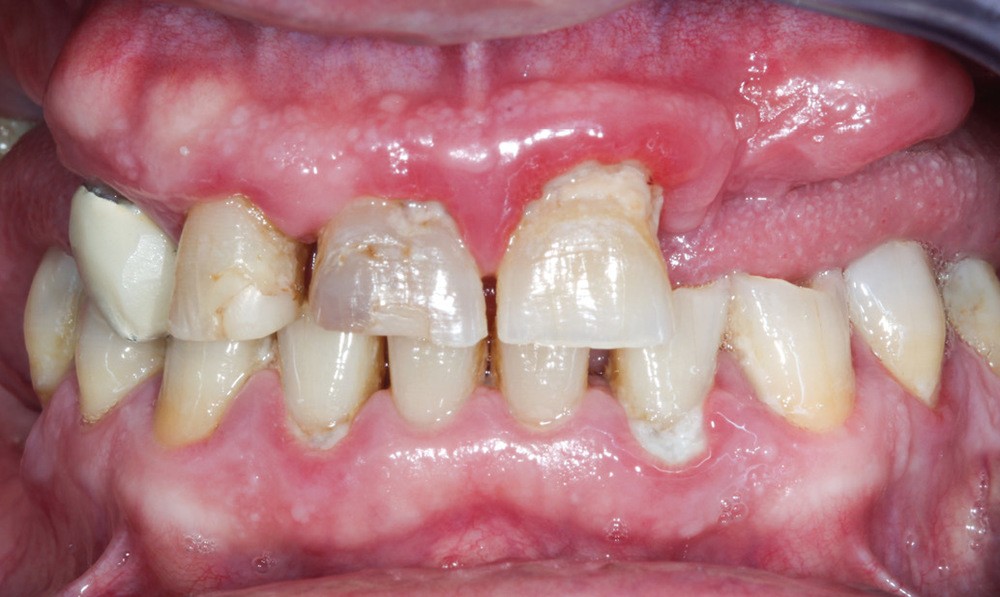

Situation thérapeutique

Un patient consulte pour une prise en charge implantaire, il n’a pas de problème de santé particulier et une demande axée sur de la prothèse fixée, sans passage par une prothèse amovible temporaire si possible.

L’arcade antagoniste sera également à prendre en charge afin d’obtenir des calages molaires.

Première décision thérapeutique (janvier 2019) (fig. 1 à 3)